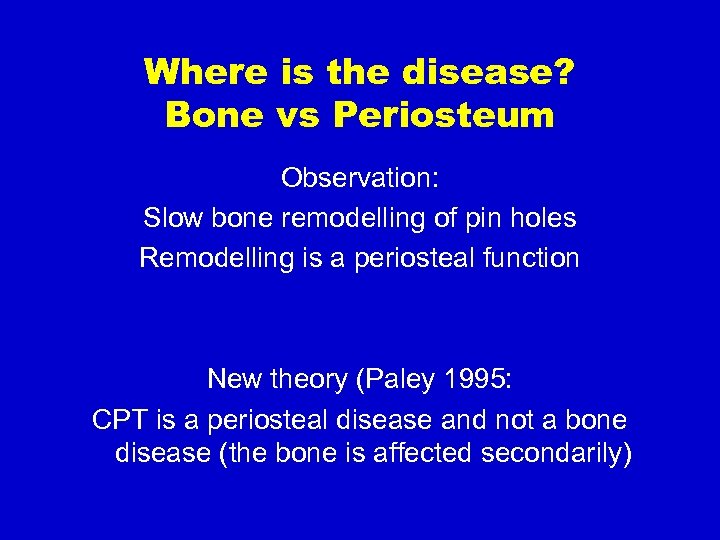

Where is the disease? Bone vs Periosteum Observation: Slow bone remodelling of pin holes Remodelling is a periosteal function New theory (Paley 1995: CPT is a periosteal disease and not a bone disease (the bone is affected secondarily)